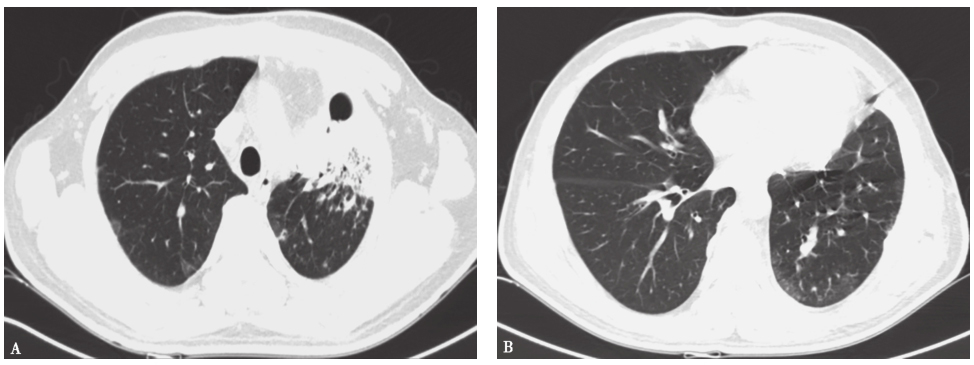

入院治疗后,复查胸部CT见左肺上叶前内段大片状密度增高影,范围较前缩小,内可见含气支气管征,边界模糊,平扫CT值约37HU。双肺内、胸膜下散在大小不等结节状密度增高影,部分较前缩小,小部分较前增大,总体较前好转,边缘模糊,较大者仍位于右下叶背段,气管支气管通畅,纵隔多个小淋巴结,大致同前。左侧胸腔后部少量弧形液性密度灶(图4)。

图4 发病第4个月胸部CT表现

胸部CT可见左上肺大片高密度影伴双肺多发结节灶

患者入院后所做系列检查显示:①患者白细胞及中性粒细胞、降钙素原、C反应蛋白、D-二聚体、血沉增高,提示存在感染;②自身抗体及ANCA均阴性,结合临床表现,基本可以排除结缔组织疾病;③支气管镜检查见后支外压闭塞,前支及尖支狭窄,远端见白色物;④胸部CT可见渗出实变范围缩小,部分结节变小,边缘模糊;这些结果均支持本病例为感染性病变。